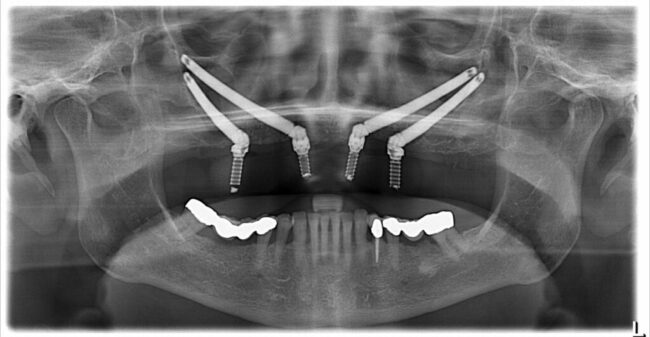

Embracing Technology: Digital Innovations in Implant Dentistry

Transforming Dentistry Through Technology In the field of dentistry, the gentle whisper of technological advancements is crafting a tapestry where science, innovation, and artistry converge to reimagine implantology. The journey of dental implants, once reliant on manual dexterity and clinical acumen, now intertwines with the precision and possibilities ushered in by digital innovations. The Fusion…